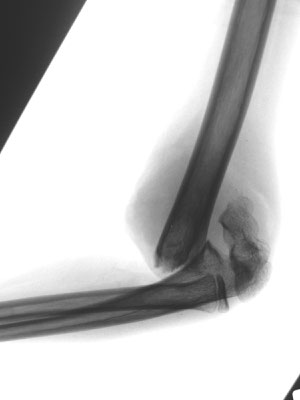

8-jähriger Junge mit ellenbogennahem Oberarmbruch. Der Bruch musste operativ eingerichtet werden. Stabilisierung mit Drähten, Gips für 3 Wochen. Die Drähte werden nach 3 Monaten wieder entfernt.